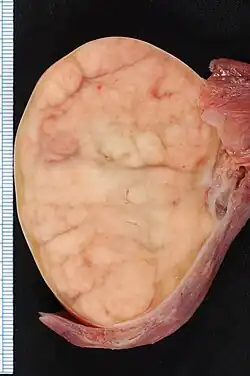

Zaadbalkanker[1] of testiscarcinoom is een vorm van kanker die ontstaat in de zaadbal, ook wel testis of testikel genoemd.

Zaadbalkanker ontstaat meestal in kiemcellen, de cellen in de zaadbal die het zaad produceren.